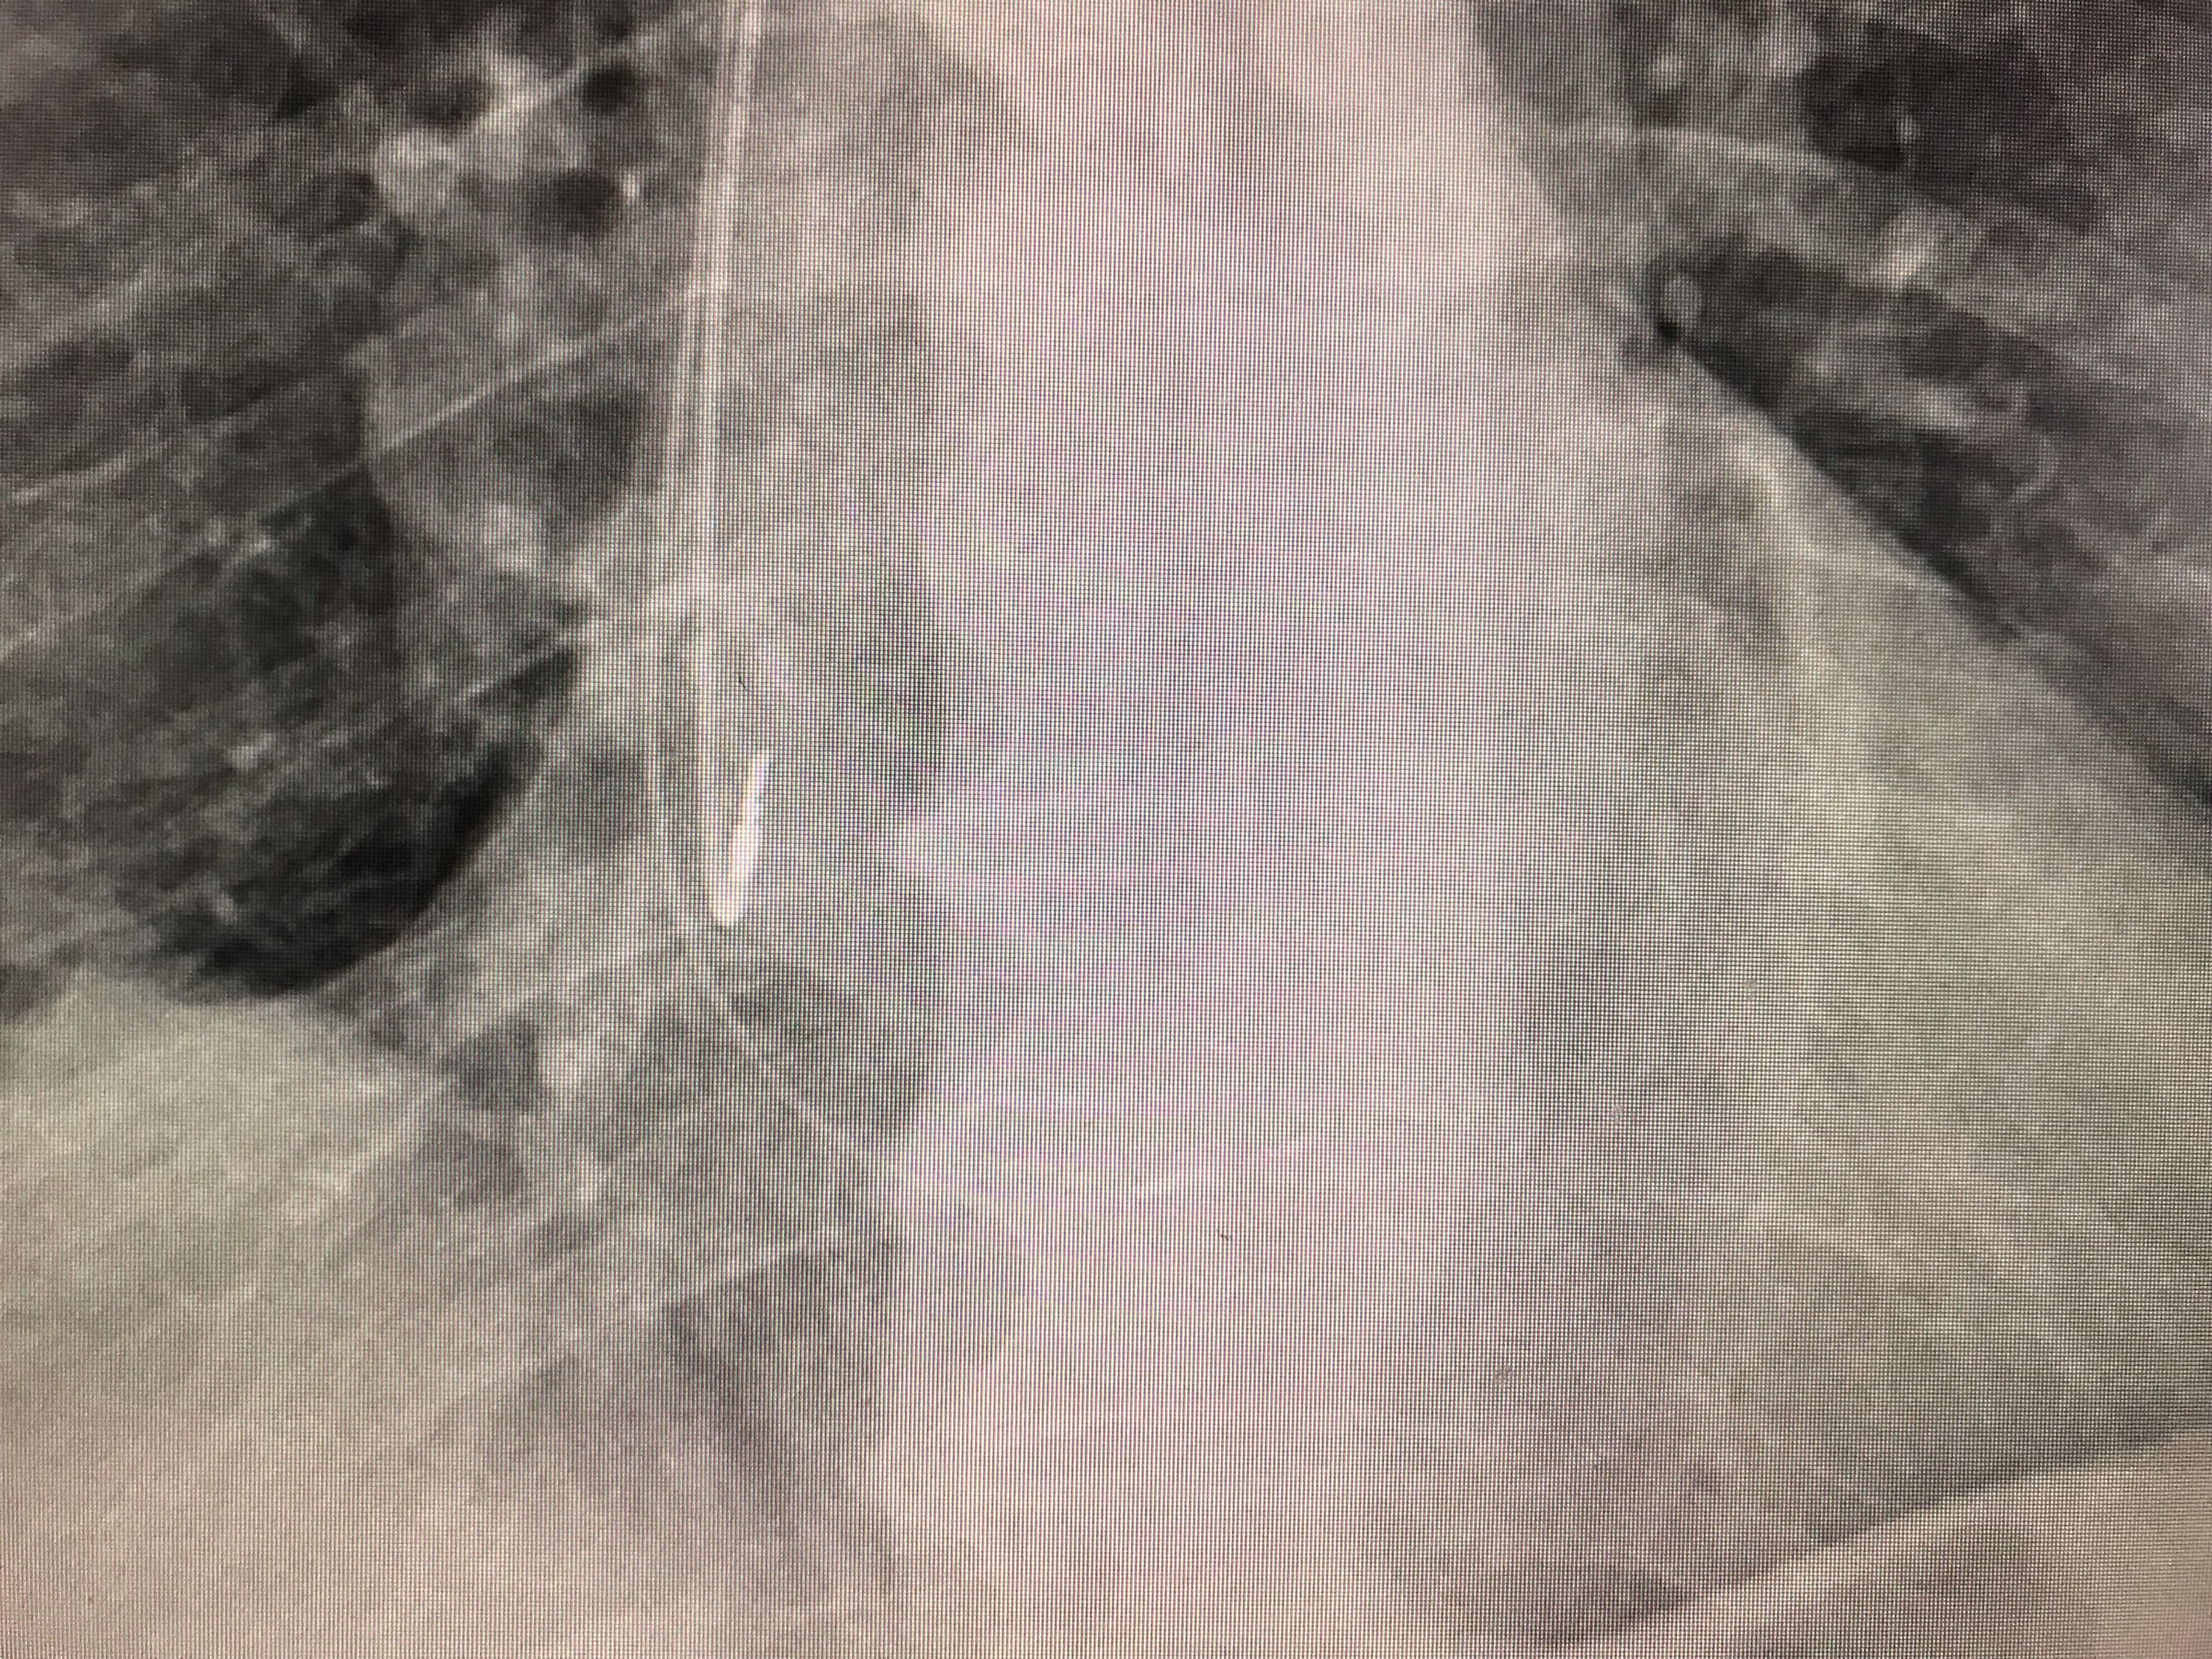

Podczas zabiegu klasycznego, prawokomorową elektrodę stymulatora serca implantuje się w przegrodę międzykomorową lub w koniuszek prawej komory. Zawsze prowadzi to do zaburzeń synchronii skurczu komór serca, a często do różnego stopnia pogorszenia tolerancji wysiłku. Stymulacja pęczka Hisa jest najdoskonalszą metodą stymulacji, bo nie burzy synchronii skurczu komór i praktycznie przywraca fizjologiczną sekwencję stymulacji serca.